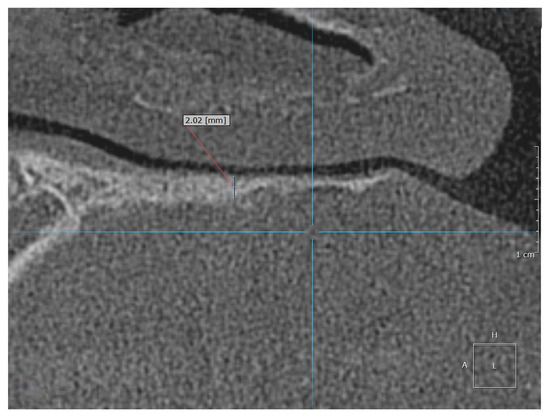

The HPT was measured at maximum magnification in the Picture Archiving and Communication System (=PACS). We defined the measurement point for HPT on the left dorsal third of the palatal process of the maxilla because the contour of the hard palate is linear here over approximately 1 cm (see Figure 1).

Examples of the measurement of normal, osteopenic, and osteoporotic patients are shown in Figure 2, Figure 3 and Figure 4.

The HPT was measured in the CBCT images by a radiologist and a dentist, independently. The defined measurement point (see Figure 1) was applied for 68 CBCT images: 52 normal and young (control group), 4 normal > 30 years old patients with DXA, and 12 patients with osteopenia or osteoporosis with DXA.

Figure 3. Example of the measurement location for an osteopenic patient.